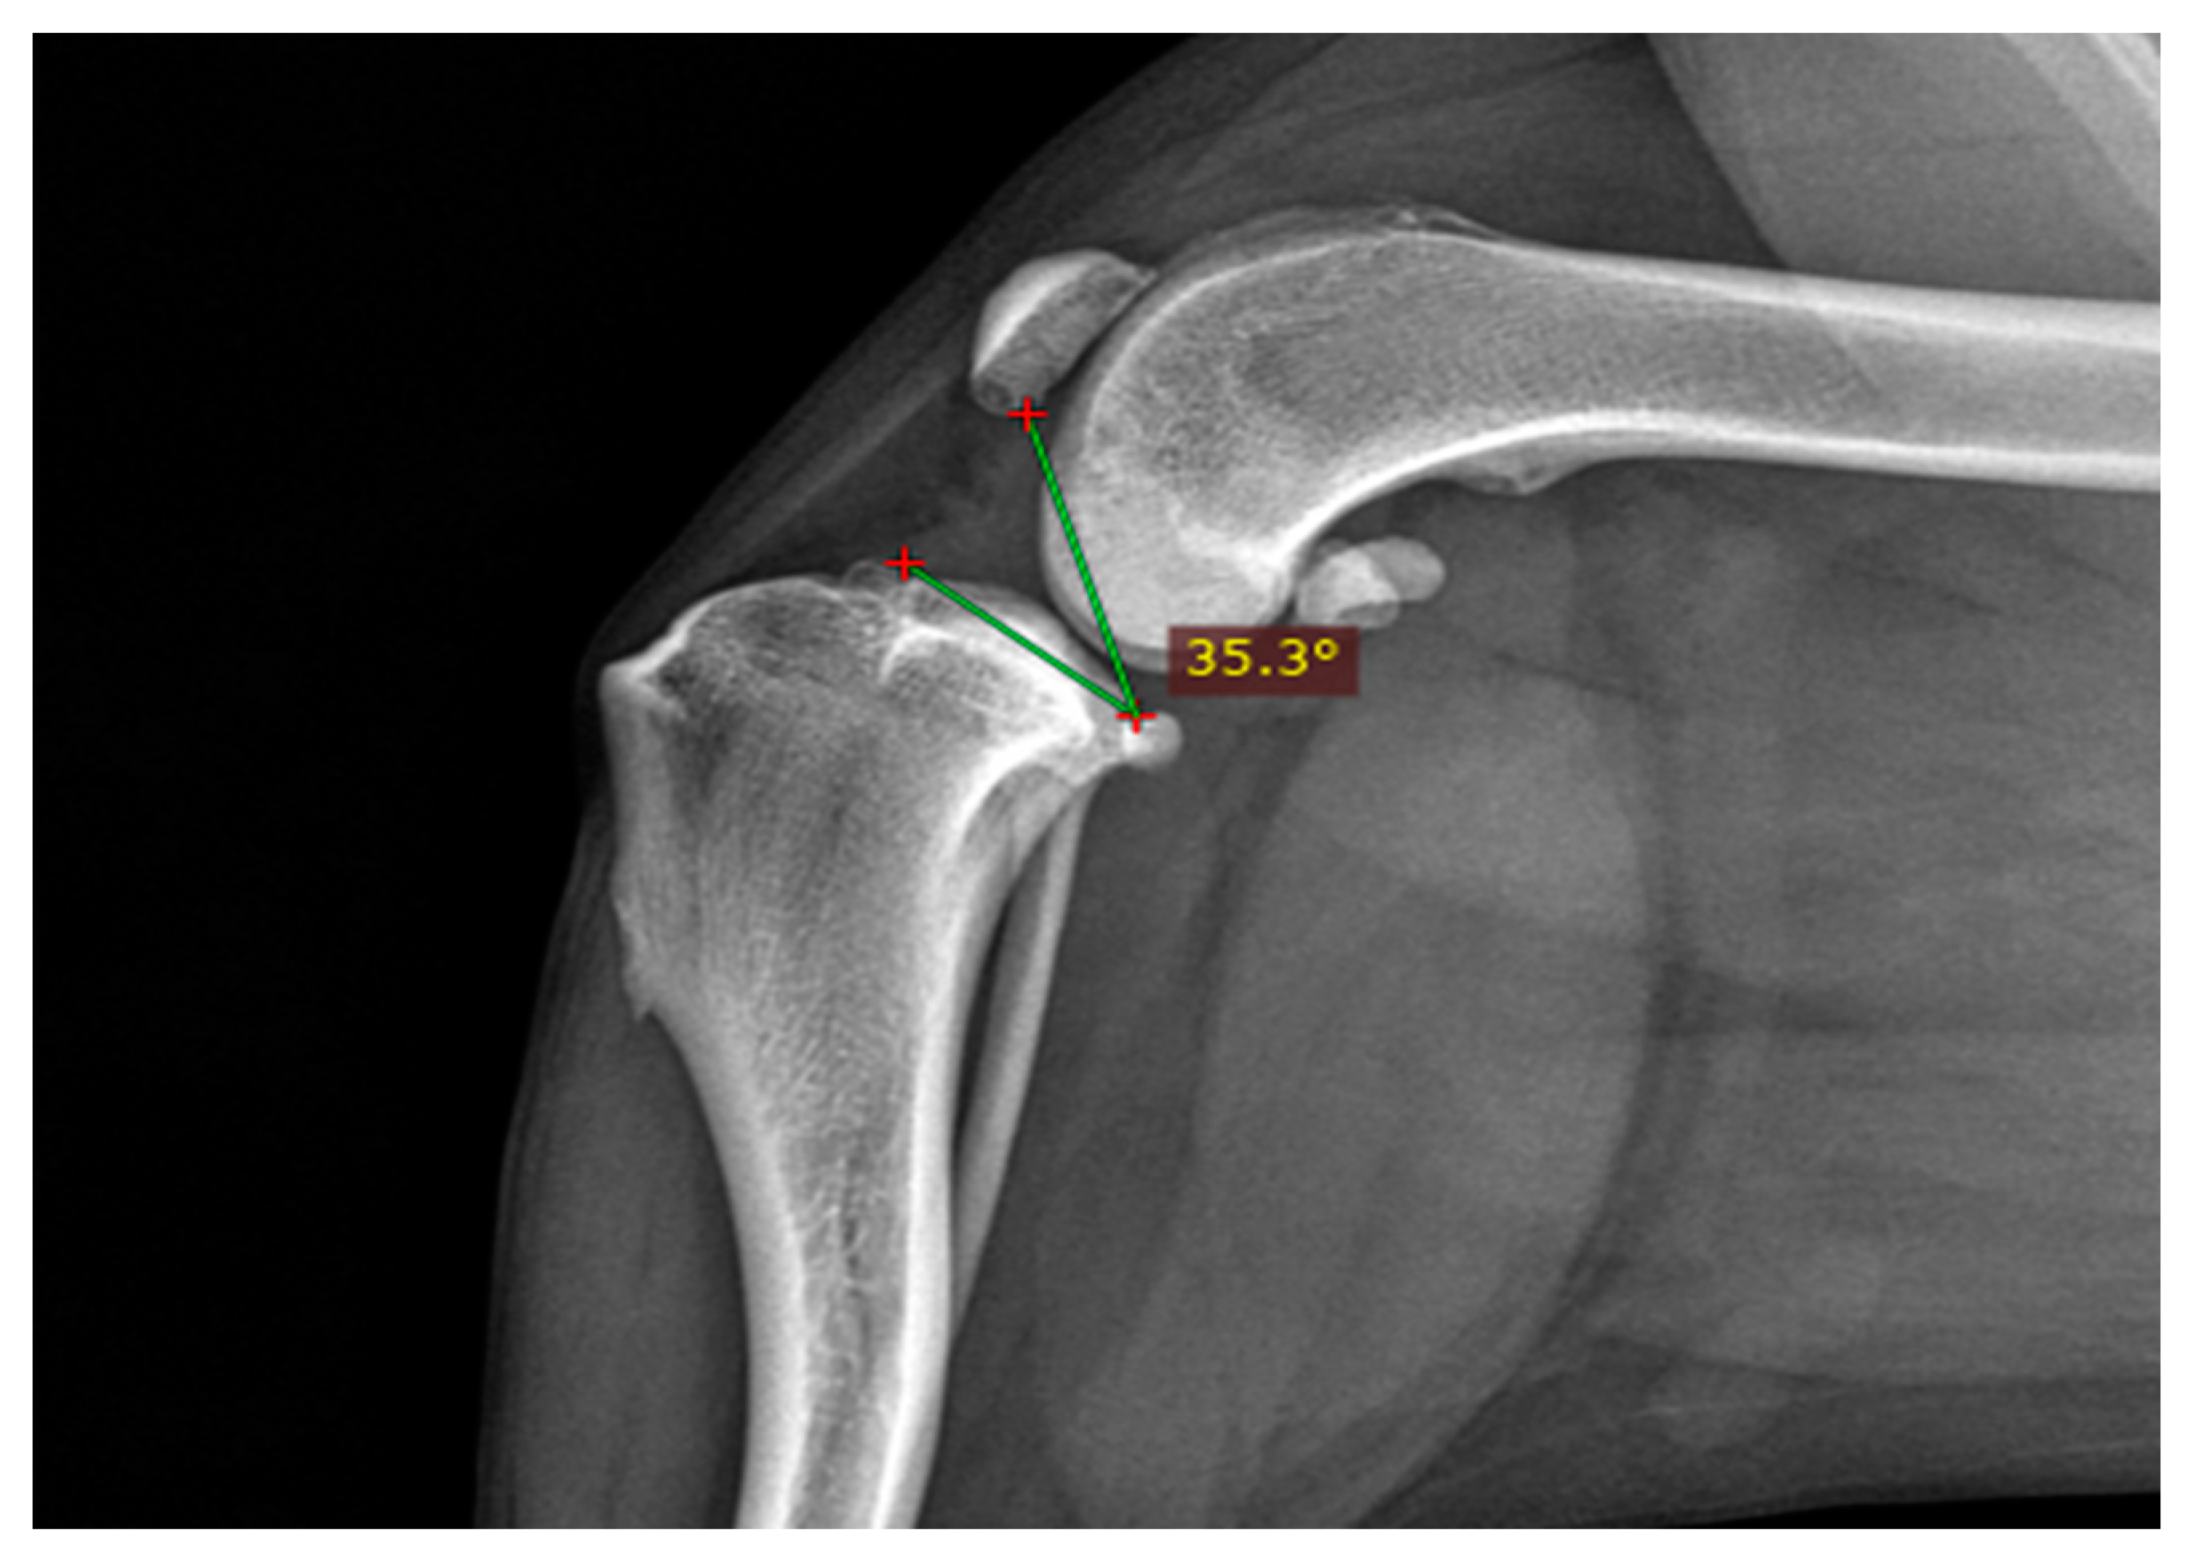

| Weight Group | Stifle Angle | Mean TPPA | ±SD 1 |

|---|---|---|---|

| ~45° | L | 43.67° | |

| M | 40.28° | ||

| S | 37.92° | ||

| Across groups 2 | 40.68° | ±4.28° | |

| ~90° | L | 35.12° | |

| M | 34.80° | ||

| S | 35.62° | ||

| Across groups | 35.26° | ±3.88° | |

| ~135° | L | 29.32° | |

| M | 26.37° | ||

| S | 28.06° | ||

| Across groups | 28.23° | ±3.54° |